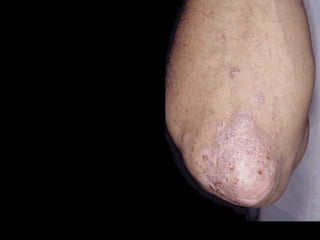

“ chronic   non-infectious   erythematous   plaques   &   papules   silvery scales   extensor distribution”

Psoriasis vulgaris   (common) Chronic  Relapsing Papulosquamous dermatitis

Erythematous plaques  with   Silver scaling

Auspitz’s sign It bleeds

Which sites are involved ?

Scalp ,  Lips no involved Oral lesions are rare

5 %  cases --- Polyarthritis